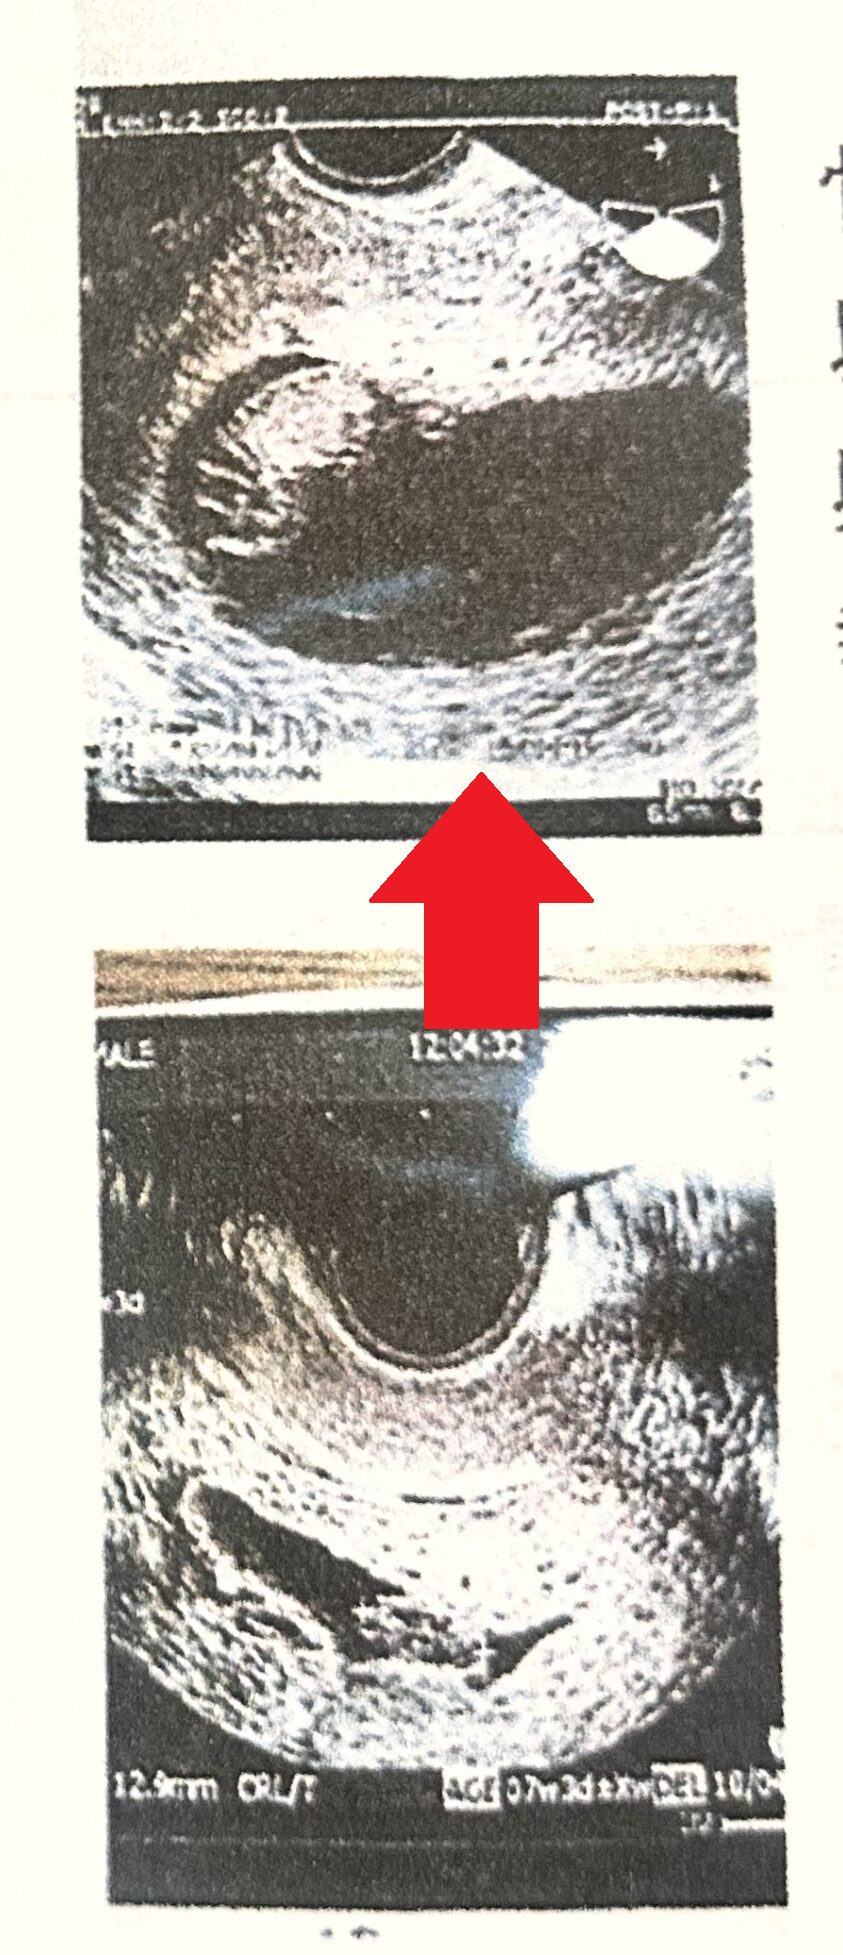

⇨

左はトコちゃんベルト着用前(7㎝の骨盤のゆるみ)⇒右は着用後(2㎝の骨盤のゆるみ) 流産歴が数度あり、今回の妊娠後も出血など不安定で来院。

左の写真で骨盤のゆるみが7㎝以上あり、子宮内の胎嚢の形状が悪いので、トコちゃんベルトを正しく着用を指導しました。 着用後は右の写真、丸くふっくらとした子宮内の胎嚢の写真になりました。(2㎝の骨盤のゆるみ) その後無事に出産されました。喜びの手紙を頂きました。

正しく着用しないと逆に骨盤のゆるみが悪化し、症状の悪化になります。正しく着用して下さい。 |